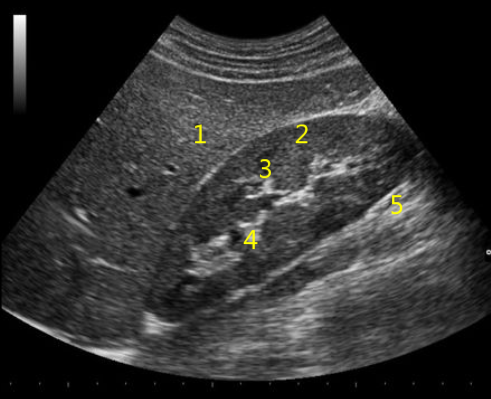

Как выглядит доля Риделя на УЗИ печени